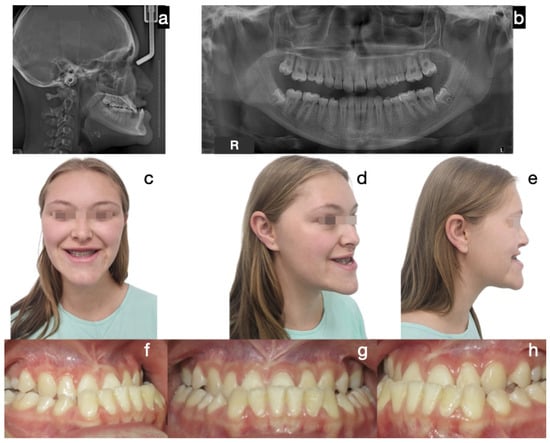

Figure 7. Case 3 corresponds to patient 9 described in Table 1. Protocol C (bilateral condylectomy followed by orthopedics and/or corrective orthodontics without second surgical intervention). Initial photos: (a) frontal extraoral photograph, (b) frontal smile photograph, (c) lateral extraoral photograph, (d) lateral skull radiograph, (e) panoramic radiograph, (f) lateral right intraoral photograph, (g) frontal intraoral photograph, (h) lateral left intraoral photograph.

Protocol C followed in frequency (cases 2, 8, and 9), a single-surgical approach, involved bilateral condylectomy followed by orthodontics and/or orthopedics to correct sagittal discrepancies, avoiding a second surgery. One of the patients who followed this protocol is the one presented in Figure 7, Figure 8, Figure 9 and Figure 10, which show a 12-year-old female patient (Case 9, Table 1) with a severe mandibular prognathism that was accentuated after menarche. Anatomically, as evidenced by radiographic images, the condyles are elongated with posterior divergence but have normal anatomy. In addition, she has a lingual offset of the lower incisors. The result of the nuclear medicine test was 1.45 for the right condyle and 1.38 for the left condyle, confirming the active state of the CH. The surgical intervention consisted of a 5 mm high bilateral condylectomy. Histopathologic examination reported a soft condyle thickness of 0.6 mm for both condyles, with positive findings for CHB. In this case, in which the sequelae in the three planes of space were not severe and, additionally, there was growth potential, it was decided to correct the sagittal relationship of the jaws with skeletally anchored orthopedics and then with corrective orthodontics to achieve an ideal occlusion. In the active phase, the treatment lasted 24 months, and, in the follow-up phase, it lasted 48 months with adequate stability.